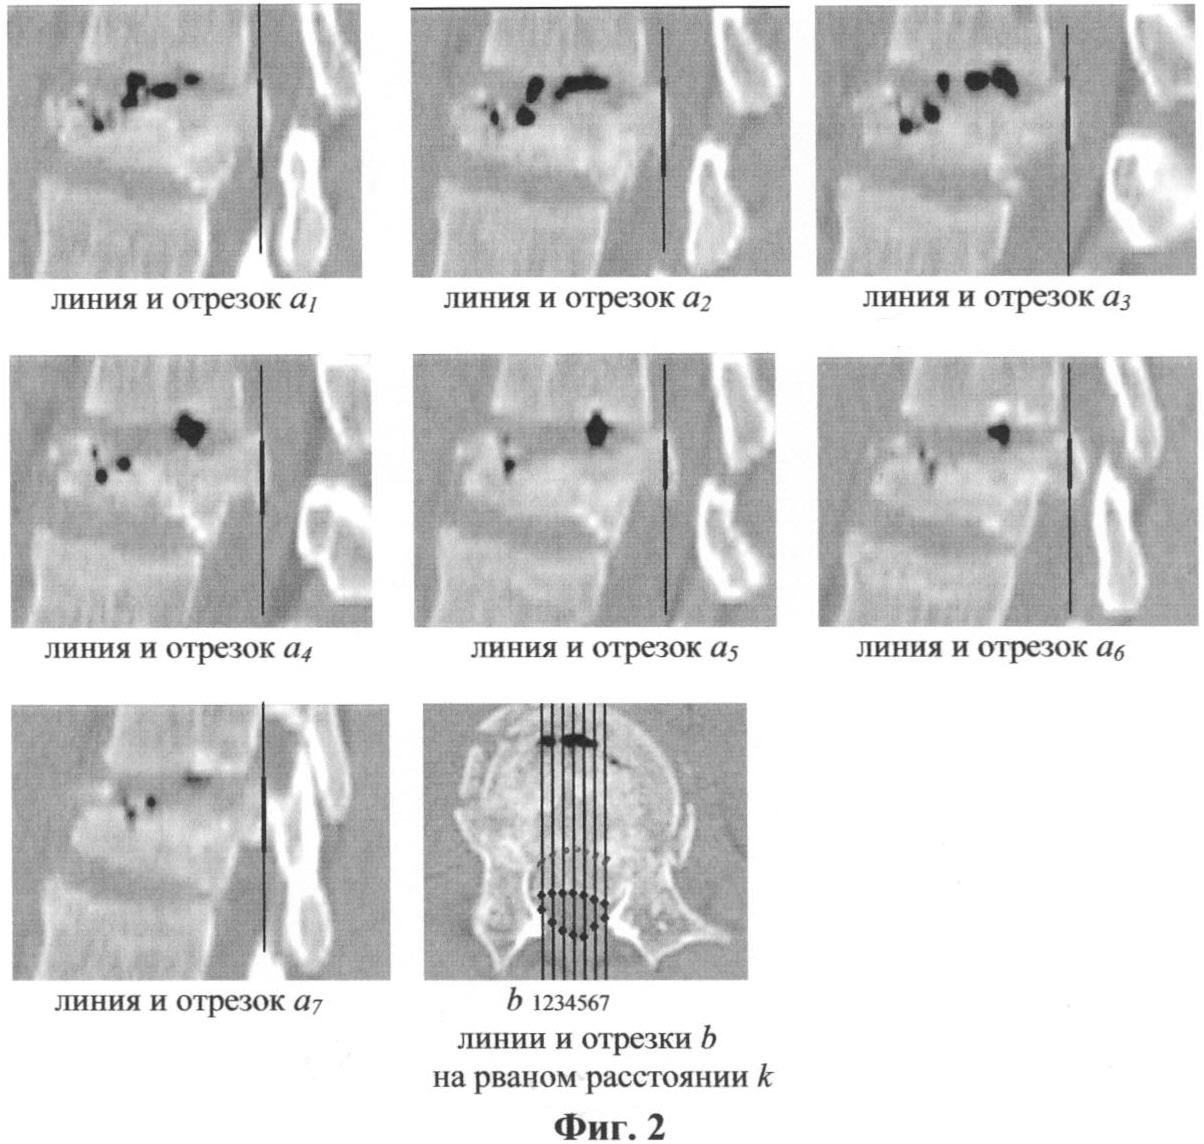

На Фиг.2 изображены продольные и аксиальные снимки поврежденного позвонка с построением линий и отрезков на них по контуру дефекта позвоночного канала.

Подробное описание заявляемого способа количественной оценки дефицита объема позвоночного канала на уровне дефекта пораженного сегмента. Предварительным этапом количественной оценки дефицита объема являются следующие действия «материального» характера: снятие томограмм продольного и поперечного сечений позвоночника в одинаковом масштабе. Два этих изображения совмещают таким образом, чтобы границы дефекта совпали. Затем осуществляют дополнительное построение ряда вспомогательных прямых линий (М). Прямые проводят через равные расстояния (k, мм) друг от друга, параллельно друг другу и перпендикулярно оси позвоночника, пересекая контуры дефектов одновременно на обоих совмещенных изображениях. Отрезки, заключенные внутри контуров дефекта на изображениях, имеют длины ai (мм) в продольном сечении и bi (мм) в поперечном для каждой i-й построенной прямой. Для примера, представленного в заявке, М=7 (число прямых). Для каждой, например, из семи построенных прямых, контурами дефекта в позвоночном канале на изображениях продольного и поперечного сечений, соответственно, выделяют отрезки: длиной а1 и b1 для линии i=1, а2 и b2 для линии i=2 и т.д.